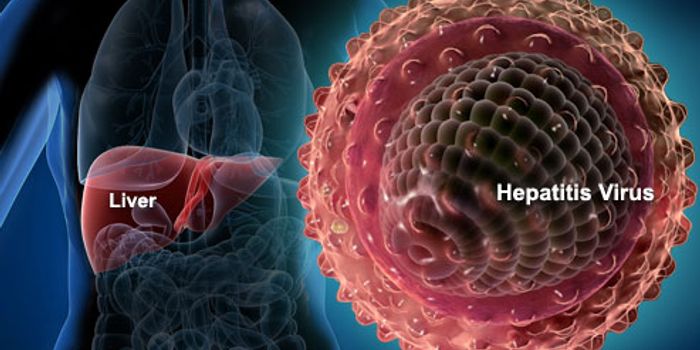

APR 08, 2015ImmunologyAn over-the-counter drug indicated to treat allergy symptoms limited hepatitis C virus activity in infected mice, accord ...

OCT 06, 2015ImmunologyThe Nova Scotia Health Authority in Canada is leading a hepatitis C study at the Prince Edward Island's (PEI) provin ...